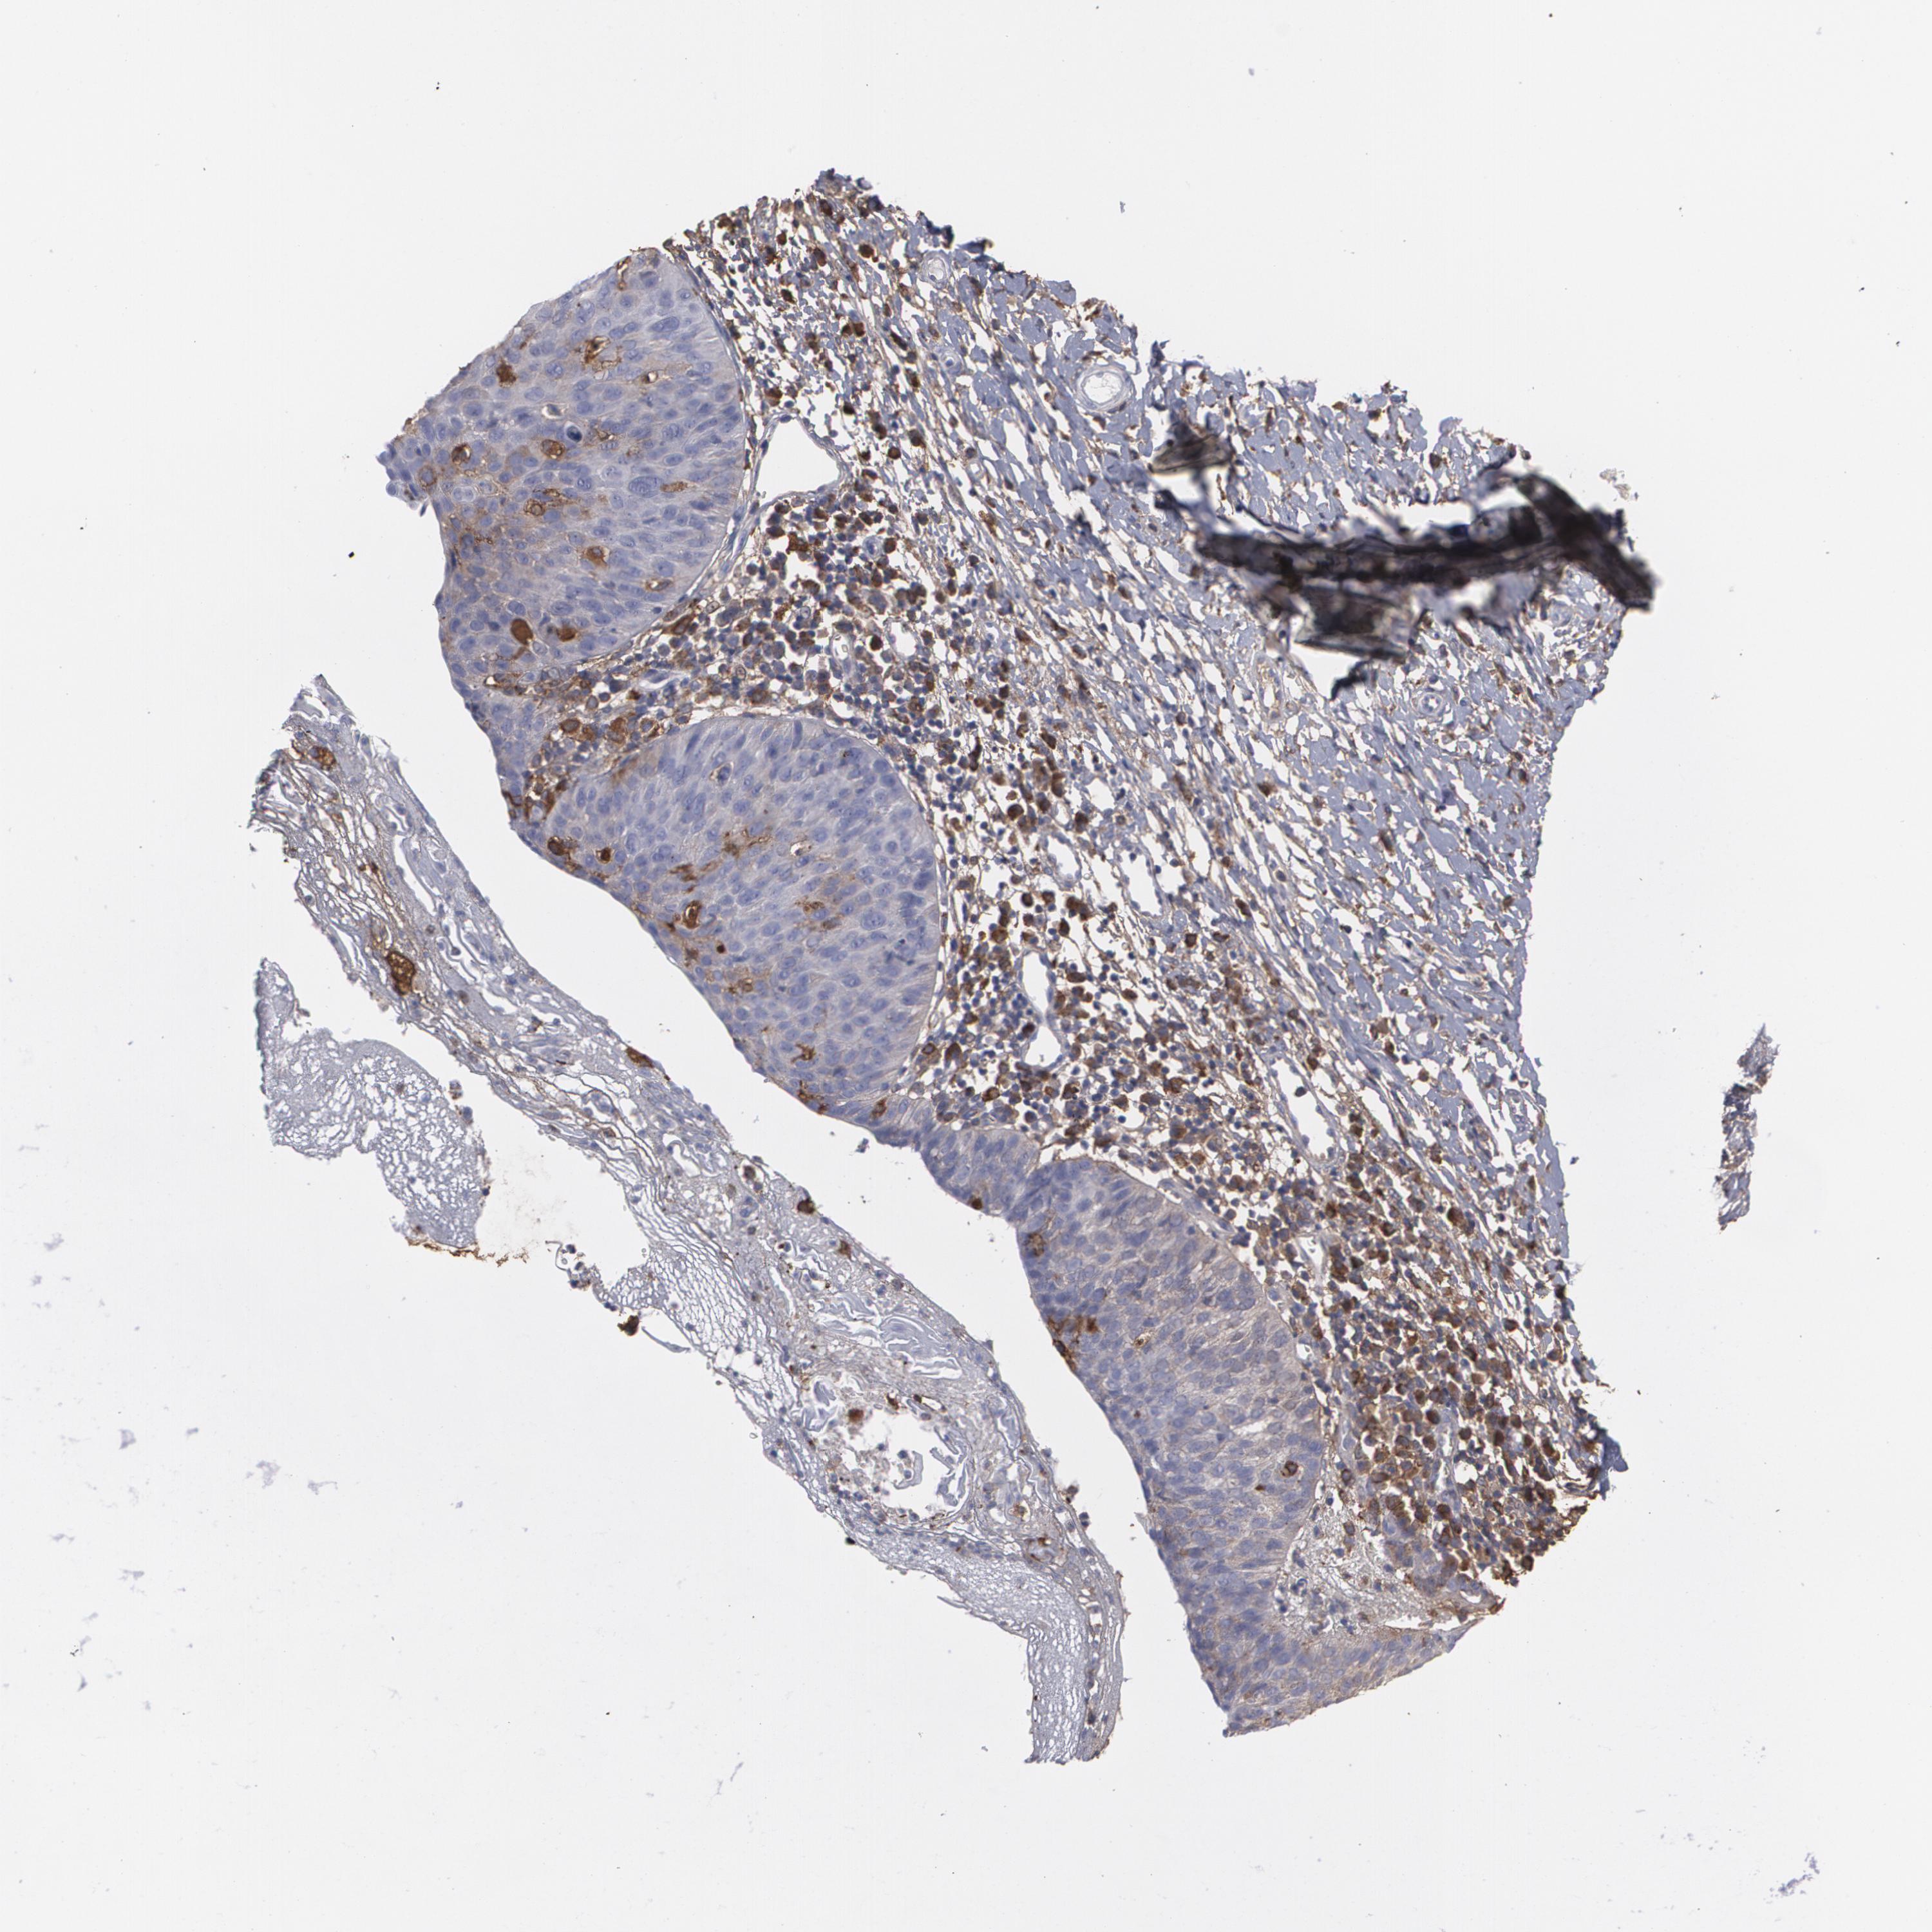

CERVICAL CANCER - Protein expressioni

A mouse-over function shows sample information and annotation data. Click on an image to view it in a full screen mode. Samples can be filtered based on level of antibody staining by selecting one or several of the following categories: high, medium, low and not detected. The assay and annotation is described here.

Note that samples used for immunohistochemistry by the Human Protein Atlas do not correspond to samples in the TCGA dataset.

Antibody stainingi

Antibody staining in the annotated cell types in the current human tissue is reported as not detected, low, medium, or high, based on conventional immunohistochemistry profiling in selected tissues. This score is based on the combination of the staining intensity and fraction of stained cells.

Each image is clickable and will lead to virtual microscopy that enables deeper exploration of all samples and also displays staining intensity scores, fraction scores and subcellular localization as well as patient and tissue information for each sample.

Antibody HPA001536

Antibody CAB035996

Staining

High

Medium

Low

Not detected

Intensity

Strong

Moderate

Weak

Negative

Quantity

>75%

75%-25%

<25%

None

Location

Nuclear

Cytoplasmic/membranous

Cytoplasmic/membranous,nuclear

Squamous cell carcinoma, NOS

Adenocarcinoma, NOS